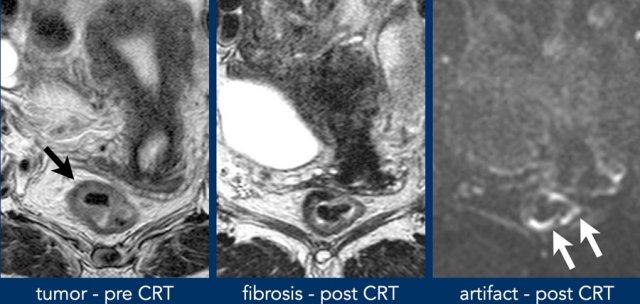

Sau hóa xạ trị, các khối u trực tràng thường co nhỏ lại và trải qua quá trình biến đổi xơ hóa, biểu hiện dưới dạng giảm tín hiệu T2 rõ rệt tại vùng nền khối u.

Phân biệt xơ hóa với khối u còn sống sót vẫn còn là một thách thức.

Tín hiệu T2 không đồng nhất hoặc hiệu ứng khối tồn tại trong xơ hóa làm tăng nghi ngờ về bệnh còn sót lại.

DWI cải thiện đáng kể độ chính xác bằng cách phát hiện các vùng khuếch tán hạn chế trong xơ hóa.

- Hình ảnh T2-weighted phân giai đoạn ban đầu và phân giai đoạn lại cho thấy vùng nền khối u chủ yếu xơ hóa với tín hiệu không đồng nhất nhỏ (mrTRG 3) sau hóa xạ trị.

- Hình ảnh DWI tái giai đoạn cho thấy vùng tín hiệu cao khu trú tại bờ trong của xơ hóa, với tín hiệu ADC thấp, cho thấy sự khuếch tán bị hạn chế.

- Mô bệnh học xác nhận đây là phần mô u còn sót lại nhỏ (ypT2)

Hình ảnh

- Trước CRT: CRT:

khối u ở thành trực tràng trước bên phải (mũi tên đen). - Xơ hóa sau CRT hiện diện ở vùng nền khối u cũ (9–12 giờ).

- DWI: Tín hiệu cao

(mũi tên trắng) nằm ở phía đối bên, ngoài

vùng khối u ban đầu.

Điều này gây ra bởi hiện tượng nhiễu ảnh do độ cảm từ từ khí trong lòng trực tràng.

Luôn luôn đối chiếu vị trí của tín hiệu DWI cao với vị trí khối u ban đầu.